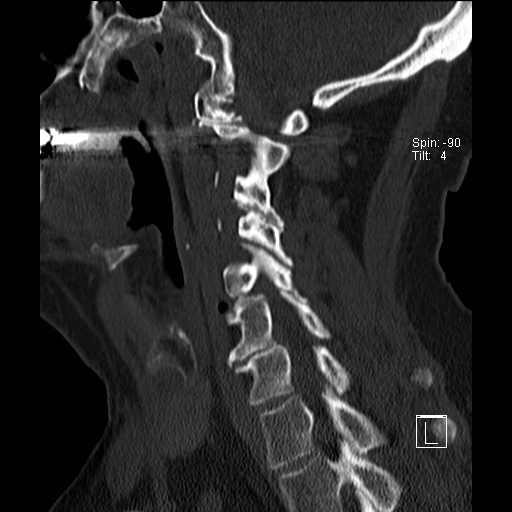

Lồng nền sọ

Lồng nền sọ, còn gọi là sụt lún sọ não hay ấn nền sọ, xảy ra ở 5-10% bệnh nhân viêm khớp dạng thấp cột sống cổ.

Trong lồng nền sọ, mỏm răng sa vào lỗ chẩm làm thu hẹp không gian dành cho tủy sống.

Biểu hiện lâm sàng đa dạng, từ đau đầu mạn tính, hạn chế vận động cổ đến suy giảm thần kinh cấp tính (chèn ép tủy sống và thân não, có thể dẫn đến liệt hoặc thậm chí tử vong nếu cổ bị di chuyển ở một số tư thế nhất định).

Hình ảnh

Cuộn xem các lát cắt CT.

Có hình ảnh di chuyển lên trên của mỏm răng vào lỗ chẩm.